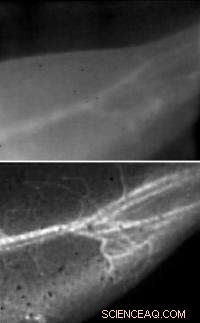

These images of a mouse's blood vessels show the difference in resolution between traditional near-infrared fluorescence imaging (top) and Stanford's new NIR-II technique (bottom).

(Phys.org)—Stanford scientists have developed a fluorescence imaging technique that allows them to view the pulsing blood vessels of living animals with unprecedented clarity. Compared with conventional imaging techniques, the increase in sharpness is akin to wiping fog off your glasses.

That the nanotubes fluoresce at substantially longer wavelengths than conventional imaging techniques is critical in achieving the stunningly clear images of the tiny blood vessels: longer wavelength light scatters less, and thus creates sharper images of the vessels. Another benefit of detecting such long wavelength light is that the detector registers less background noise since the body does not does not produce autofluorescence in this wavelength range.